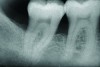

A series of full-mouth diagnostic radiographs that visualize each tooth or implant are critical as a baseline (Figure 11). The frequency and type of radiographs needed at maintenance depends on the severity of periodontal disease, as well as the extent of restorative treatment and caries susceptibility. With more advanced periodontal disease and restorative concerns, more frequent radiographs may be indicated. Vertical bitewing radiographs provide a better view of osseous crest levels and should be considered over horizontal bitewing radiographs for periodontal cases (Figure 12).

Fig 9. X-ray shows bone loss on the distal aspect and in the area of the furcation of tooth No. 31.

Figure 9

Fig 10. Postoperative x-ray depicts bone fill of the defect 2 years after regenerative therapy.

Figurer 10

Fig 12. Vertical bitewing radiographs.

Figure 12